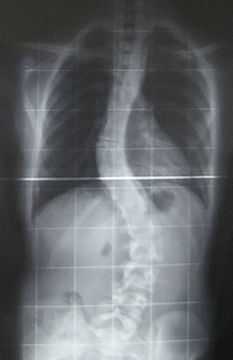

Костная система: болезнь характеризуется карликовостью (рост взрослого больного около 80-115 см), непропорциональным телосложением (относительно короткое туловище, микроцефалия, короткая шея). Выражена деформация скелета, особенно грудной клетки (куриная, бочкообразная, килевидная). Отмечается кифосколиоз грудного и поясничного отделов позвоночника, при тугоподвижности крупных суставов определяется расслабление связочного аппарата в мелких суставах, что приводит к их гипермобильности. Выявляются контрактуры в локтевых, плечевых, коленных суставах; вальгусная деформация нижних конечностей, плоскостопие.

Комментарии: выявляются деформации скелета, особенно грудной клетки (куриная, бочкообразная, килевидная), кифосколиоз грудного и поясничного отделов позвоночник. Выявляются уплощение и расширение тел позвонков, чем объясняется характерное укорочение туловища и необычно короткая шея. Выраженный углообразный кифоз. Рентген длинных трубчатых костей выявляет недоразвитость эпифизов, укорочение костей предплечья: локтевая кость не достигает лучезапястного сустава. Изменены кости таза: вертлужные впадины плоские и широкие, их крыша скошена, крылья подвздошных костей неправильной формы; контуры всех костей неровные; головки бедренных костей уплощены.

Прогноз этого подтипа MD указывает на то, что пострадавший человек может в конечном итоге иметь трудности с кормлением. В какой-то момент хирургическое вмешательство может быть вариантом лечения сколиоза.

Сколиоз, который представляет собой искривление позвоночного человека в сторону, определяется множеством факторов, включая степень (легкая или тяжелая), и в этом случае если возможно, человек может использовать бандаж.

Сколиоз, который представляет собой изгиб позвоночника вбок, определяется множеством факторов, включая степень (легкая или тяжелая), и в этом случае, если возможно, человек может использовать скобу. [12]